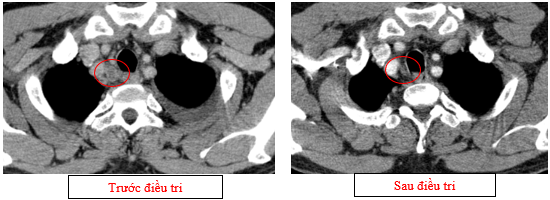

-         Chụp cắt lớp vi tính lồng ngực (11/2025): Màng phổi vùng rốn phổi trái dày,dày tổ chức kẽ vùng ngoại vi đáy phổi hai bên. Màng phổi trái có vài nốt đặc ngấm thuốc nốt lớn nhất kích thước 17x15mm. Khoang màng phổi hai bên không có dịch – khí (Tổn thương giảm đáng kể so với phim chụp 08/2025). Trung thất, rốn phổi hai bên, hố thượng đòn trái có vài hạch, hạch lớn nhất kích thước 12x6mm. Vài nốt đặc xương rải rác thân đốt sống, các cung xương sườn hai bên.

Hình 07: Hạch thượng đòn trái giảm đáng kể kích thước, từ 22mm còn 7mm sau điều trị.

Hình 10: Không còn thấy tổn thương hạch trung thất nhóm 2 sau điều trị